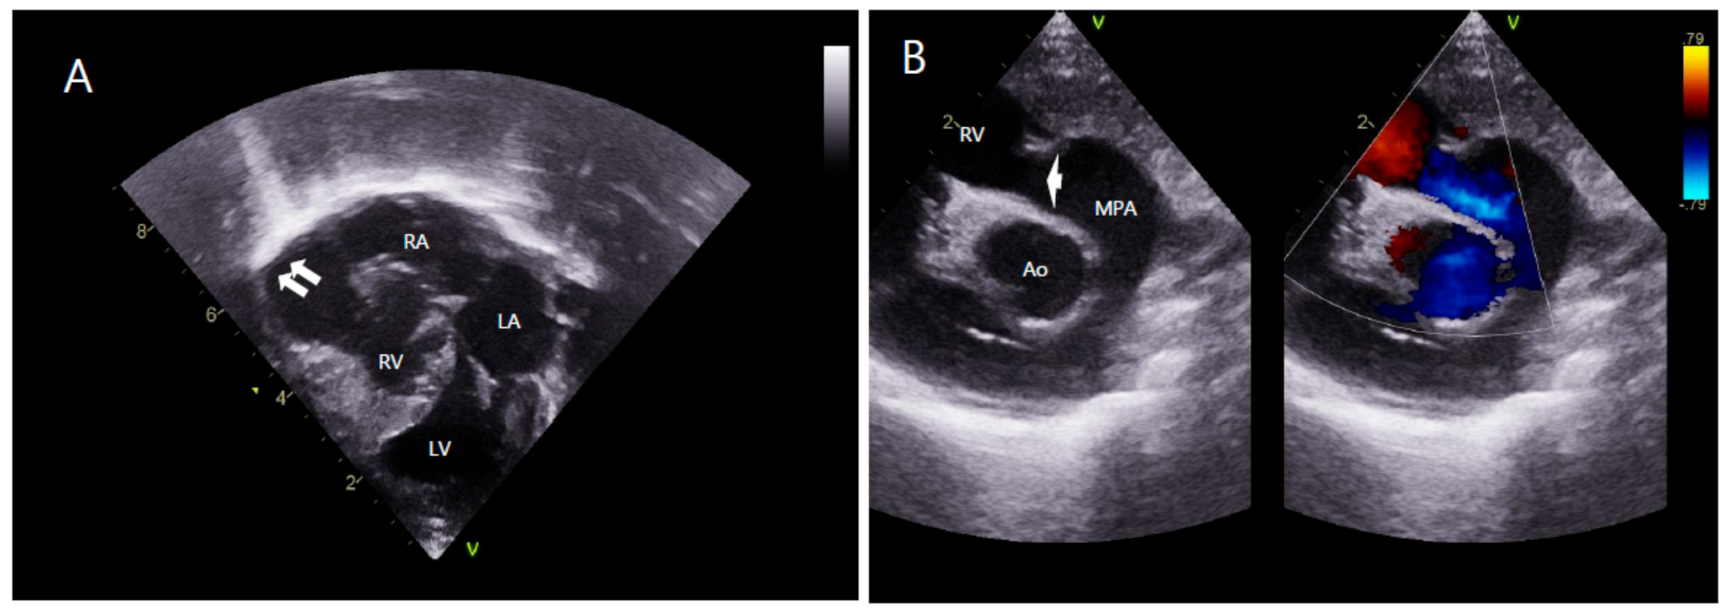

A Case of Prenatally Diagnosed Uhl’s Anomaly with Absent Pulmonary Valve Leaflets and Dysplastic Tricuspid Valve